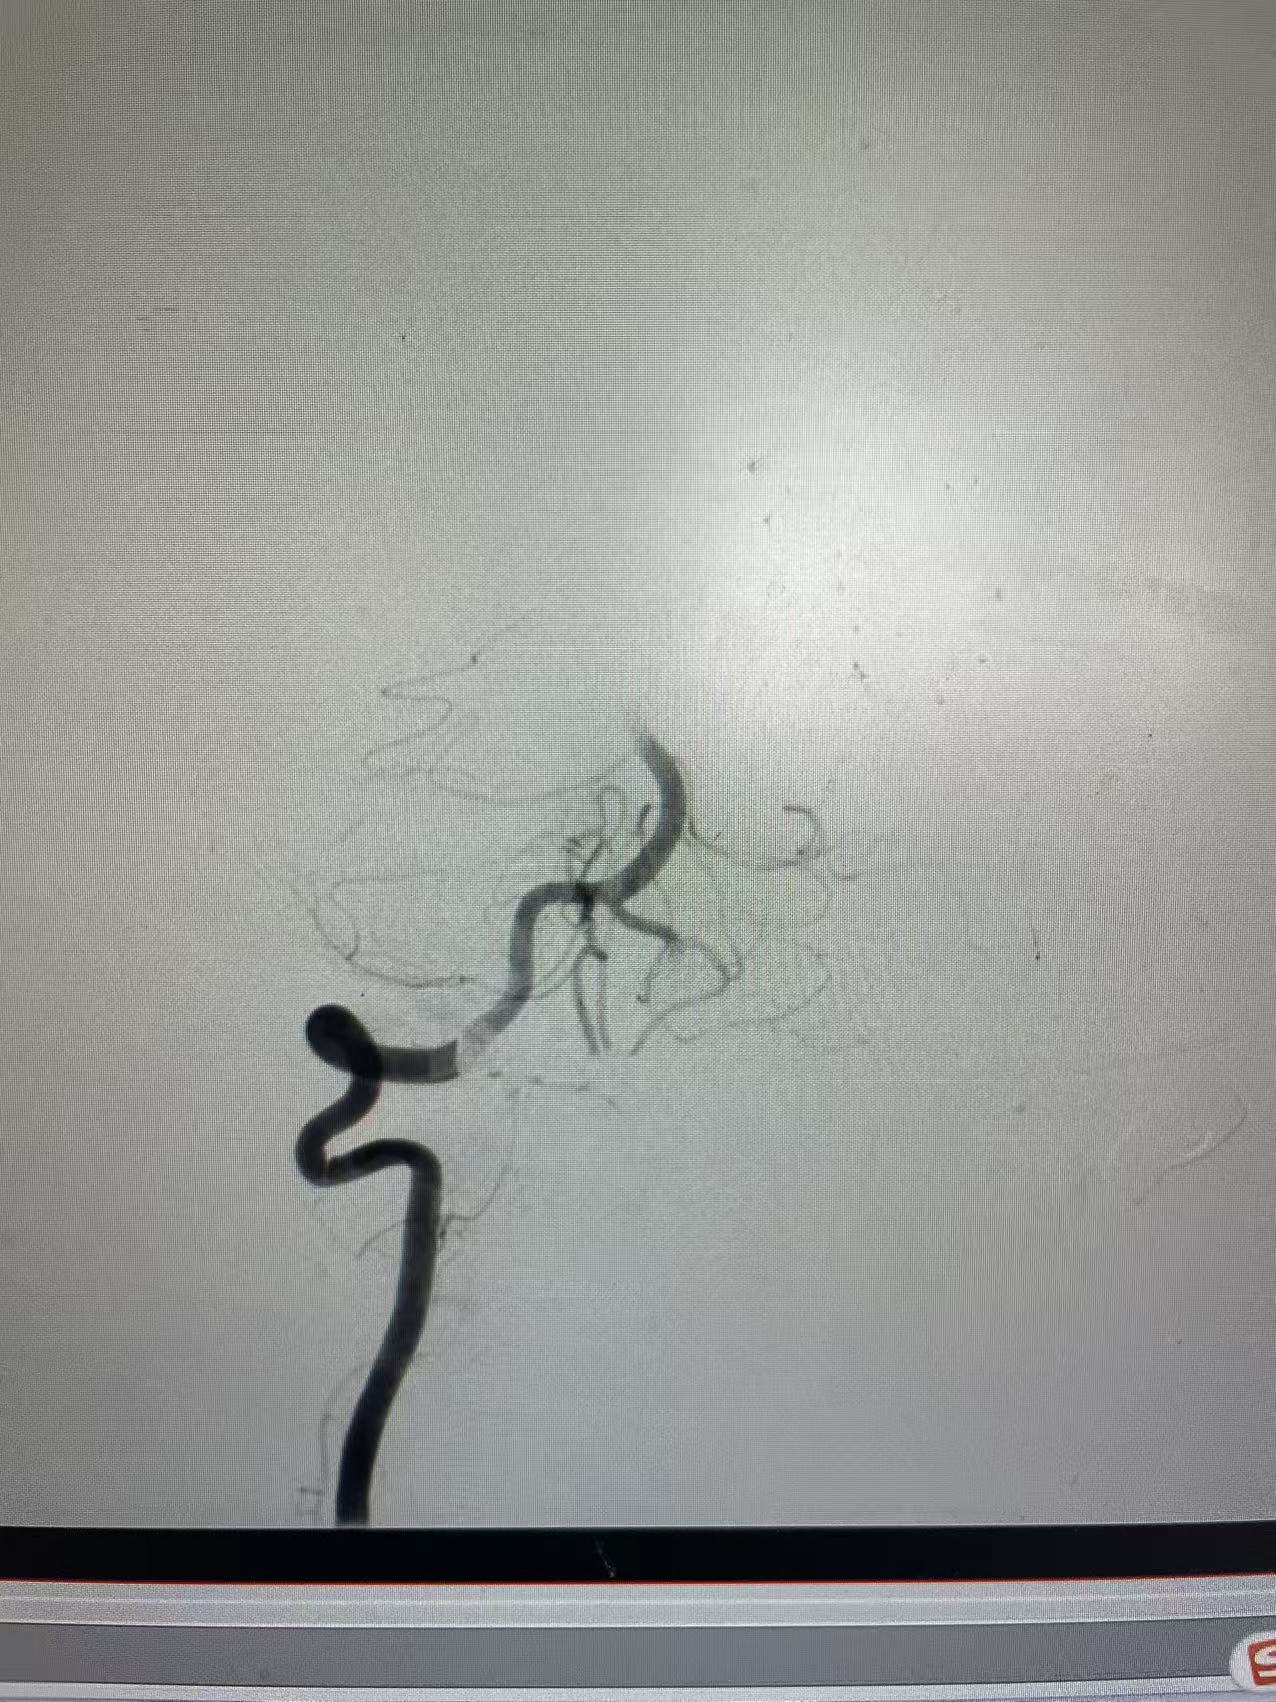

警报拉响,生命竞速立即开始。神经内科介入团队第一时间抵达战场,麻醉科、介入室同步进入“战时状态”。穿刺、造影、定位、取栓……所有动作一气呵成,团队配合如同精密齿轮,取出的血栓赫然在目。最终,仅用15分钟,成功疏通“生命通道”,为患者大脑功能的恢复赢得了决定性时机。